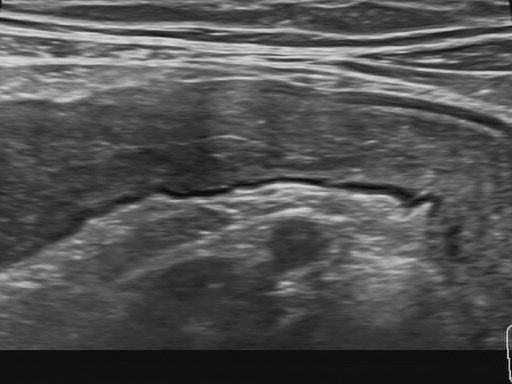

12 – Kanal EKG

Aufzeichnung der elektrischen Herzaktivität mittels 12 Ableitungen zur Beurteilung von Herzrhythmus, Herzfrequenz und Erregungsleitung. Die Untersuchung dient der Erkennung von Herzrhythmusstörungen, Leitungsstörungen oder Hinweisen auf strukturelle Herzveränderungen. Sie ist schmerzfrei, nicht invasiv und dauert nur wenige Minuten.